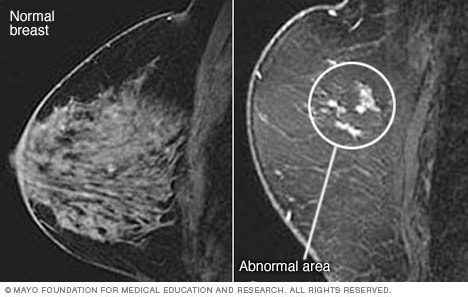

打印 概述乳腺磁共振成像(MRI)也称为乳腺 MRI,是一种用于检测乳腺癌的检查。它还可以在乳腺出现其他问题时排除乳腺癌的可能性。 乳腺 MRI 生成乳房内部的图片。它使用强磁铁、无线电波和电脑来生成细节丰富的图像。 乳腺 MRI 可能在活检发现癌症后进行。乳腺 MRI 可以显示癌变范围或另一侧乳房的问题。 乳腺 MRI 也可以与乳腺 X 线摄影一同用作筛查工具,以检测部分患者是否患有乳腺癌。这包括乳腺癌高风险人群。还包括有严重乳腺癌家族病史的人群,或者携带家族遗传的乳腺癌突变基因(遗传)的人群。产品与服务A Book: Beyond Breast Cancer 目的乳腺 MRI 用于检查乳房内是否存在其他可能患癌的区域。它也被用于筛查患乳腺癌风险较高的患者的乳腺癌情况。 如果有以下情况,您的医务人员可能会建议进行乳腺 MRI: 更多的情况是在乳腺癌诊断后同一乳房或对侧乳房出现乳腺癌。 乳房植入物可能渗漏或撕裂。 乳腺癌高风险。这意味着终身风险为 20% 或更多。风险工具会考虑家族史和其他风险因素,计算终身风险。 乳腺癌或卵巢癌的家族病史。 乳腺组织致密程度很高,乳房 X 线摄影漏诊早期乳腺癌。 存在可能导致乳腺癌的乳房病变史,乳腺癌家族病史和乳房组织密度高。包括乳腺中异常细胞的堆积,称为非典型增生,或乳腺的乳腺小叶原位癌中的异常细胞。 乳腺癌遗传基因突变在家族中传递。基因突变可以包括 BRCA1 或 BRCA2 等。 在 10 到 30 岁之间接受胸部区域的放射疗法治疗史。 如果您不确定自己是否具有高风险,请向您的医护团队成员寻求帮助,以了解您的风险情况。您可能会被转诊到乳腺诊所或乳腺健康专家。专家可以与您讨论您的风险、筛查选择以及降低患乳腺癌风险的方法。 乳腺 MRI 通常应与乳腺 X 线摄影或其他乳腺成像检查一同使用。它不应该代替乳腺 X 线摄影。尽管它是一项很好的检查,但乳腺 MRI 仍然可能漏检一些乳腺癌,而乳腺 X 线摄影可以找到。 医生可能要求高风险的妇女每年进行一次乳腺 MRI 检查,与筛查性乳腺 X 线摄影大致在同一时间进行。非常高风险的妇女可能需要每 6 个月进行一次乳腺 MRI 或乳腺 X 线摄影筛查。更多信息乳腺佩吉特病乳腺癌复发性乳腺癌导管原位癌 (DCIS)浸润性小叶癌炎性乳腺癌显示更多相关信息 申请预约 风险乳腺 MRI 是安全的。这项检查不使用辐射。与其他检查一样,乳腺 MRI 也存在风险,例如: 假阳性结果。乳腺 MRI 可能会显示需要进行更多的检查。进一步的检查,如乳腺超声或乳腺活检,可能不会显示出癌症。这些结果被称为假阳性。假阳性结果可能会引起担忧和不必要的检查。 对所使用的造影剂出现反应。乳腺 MRI 需要静脉注射钆这种造影剂,使图像更容易观察。这种造影剂可能引发过敏反应。对于肾脏问题的患者,它可能引起严重的并发症。 如何进行准备乳腺 MRI 之前的准备需要以下步骤: 在月经周期开始时预约 MRI 检查。如果您尚未绝经,MRI 设施可能更倾向于在您的月经周期中的某个特定时间进行 MRI 检查,大约在月经周期的第 5 到第 15 天之间。 月经第一天是周期的第一天。将您所处的经期阶段告知医疗机构,以便在对您来说最合适的时间安排乳腺 MRI 就诊。 将您的过敏情况告诉您的医疗护理团队成员。大多数 MRI 使用一种叫做钆的造影剂,以便更容易观察图像。这种造影剂通过手臂的静脉注入。将您的过敏情况告知医疗团队成员,这有助于预防与造影剂有关的问题。 如果您有肾脏问题,请告知您的医疗护理团队成员。常用于 MRI 成像的造影剂钆可能对患有肾脏问题者造成严重问题。 如果您已怀孕,请告知医疗护理团队:一般不建议怀孕者做 MRI 检查。这是因为造影剂可能会给胎儿带来风险。 如果您正在哺乳期,请告知医疗护理团队:如果您正在哺乳期,可能需要在进行 MRI 检查后暂停哺乳两天。美国放射学会表示,造影剂对婴儿的风险很低。不过,如果您仍不放心,可以在进行 MRI 检查后暂停母乳喂养 12 至 24 小时。 这让您的身体有时间排出造影剂。在这期间,您可以泵出母乳并将其丢弃。您可以在进行 MRI 之前泵出并储存母乳,用于喂养宝宝。 进行 MRI 检查时,不要穿戴任何带有金属的物品。MRI 可损坏金属,例如珠宝、发夹、手表和眼镜等。将带有金属的物品留在家里,或在进行 MRI 检查时取下 如果您的体内放置(植入)了任何医疗设备,请告知您的医疗护理团队成员。植入式医疗设备包括起搏器、除颤器、植入式药物端口或人工关节。 可能出现的情况 乳房核磁共振成像 打开弹出式对话框 关闭 乳房核磁共振成像 乳房核磁共振成像 进行乳房 MRI 时,需要俯卧在铺有软垫的扫描台上,乳房置入扫描台的凹陷空间。凹陷处有用于接收 MRI 信号的线圈。扫描台滑入 MRI 机器的开口。 就诊时,您可能会穿病号服或病号袍。您需要脱下衣服,摘下首饰。如果待在狭小空间会给您造成不适,请在进行乳腺 MRI 之前告知您的医疗护理团队成员。可能用药物使您放松。 可能在您的手臂上置管,通过静脉注射(IV)注入造影剂(即对比剂)。这种造影剂使 MRI 图像上的组织或血管更容易看到。 MRI 机器有一个大的中央开口。进行 MRI 时,您俯卧在带有衬垫的检查台上。检查台上有一处开口空间,乳房将置入此处。开口处设有用于接收 MRI 信号的线圈。检查台滑入机器的入口。 MRI 机器在您的周围产生一个磁场,向您的身体发送无线电波。您不会有任何感觉。但您可能听到机器内部有较大的敲打声和砰砰声。由于噪音较大,您可能会戴上耳塞。 技术人员从另一个房间进行监视。您可以通过麦克风和技术人员说话。检查过程中,保持正常呼吸,尽量躺着不动。 乳腺 MRI 就诊可能需要 30 分钟到一个小时。 结果 乳房核磁共振成像的结果 打开弹出式对话框 关闭 乳房核磁共振成像的结果 乳房核磁共振成像的结果 乳房 MRI 可找出乳房中有问题的区域。在进行乳房 MRI 之后,可能会进行乳房活检,看看在 MRI 上找到的有问题区域是否为癌症。 专门从事影像检查的医生称为放射科医师,由其检查乳腺 MRI 的图像。您的医疗护理团队成员会与您讨论检查结果。 来自妙佑医疗国际员工 申请预约 医生与科室 Jan. 05, 2024 打印 显示参考文献 Magnetic resonance imaging (MRI) — breast. RadiologyInfo.org. https://www.radiologyinfo.org/en/info.cfm?pg=breastmr. Accessed May 26, 2019. AskMayoExpert. MRI of the breast. Mayo Clinic; 2022. Slanetz PJ. MRI of the breast and emerging technologies. https://www.uptodate.com/contents/search. Accessed March 31, 2023. Monticciolo D, et al. Breast cancer screening for women at higher-than-average risk: Recommendations from the ACR. Journal of the American College of Radiology. 2018; doi:10.1016/j.jacr.2017.11.034. Bougias H, et al. Breast MRI: Where are we currently standing? Journal of Medical Imaging and Radiation Sciences. 2022; doi:10.1016/j.jmir.2022.03.072. 相关 乳房核磁共振成像 乳房核磁共振成像的结果 乳腺佩吉特病 乳腺癌 复发性乳腺癌 导管原位癌 (DCIS) 浸润性小叶癌 炎性乳腺癌 显示更多相关内容 Mayo Clinic 新闻 Exploring advanced breast cancer screening options Mayo Clinic Health System discusses advancements in breast cancer screenings Mayo Clinic Q and A: How surgery can reduce breast cancer risk Mayo Clinic Minute: MRI for dense breasts -- what to know Mayo Clinic Q&A: What do you need to know about dense breasts? 显示更多来自妙佑医疗国际的新闻 产品与服务 A Book: Beyond Breast Cancer 妙佑医疗国际明尼苏达州罗切斯特院区、妙佑医疗国际佛罗里达州杰克逊维尔院区和妙佑医疗国际亚利桑那州凤凰城/斯科茨代尔院区均在《美国新闻与世界报道》全美最佳癌症医院评选中名列前茅。 了解更多关于这一最高荣誉的信息 乳房核磁共振成像关于医生与科室 Advertisement 妙佑医疗国际不为任何公司或产品背书。广告收入为我们的非营利使命提供支持。 广告与赞助政策 政策 机会 广告选择 妙佑医疗国际出版社 浏览妙佑医疗国际出版社提供的畅销书以及书籍和简报的特别优惠。 新资讯:妙佑医疗国际睡眠改善指南 收听健康问题播客 妙佑医疗国际:关于失禁 糖尿病基本信息 妙佑医疗国际饮食方案评估 — 免费 妙佑医疗国际健康通讯 — 免费读物 PRC-20198296 医学检查与医疗程序 乳房核磁共振成像